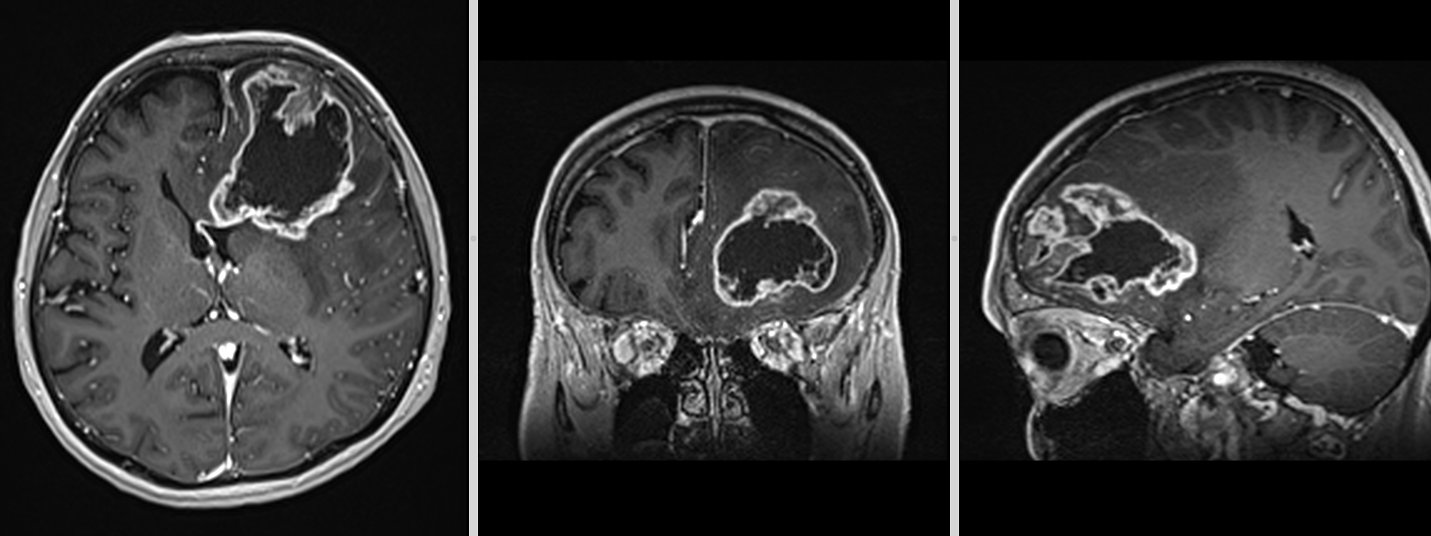

La nivel imagistic, glioblastomul apare adesea ca o leziune relativ bine delimitată, cu captare inelară de contrast și necroză centrală. Pentru ochiul neavizat, aceasta poate sugera o tumoră care ar putea fi „scoasă complet”. În realitate, ceea ce vedem pe RMN reprezintă doar componenta cea mai densă tumoral.

Imagistica – instrument esențial, dar imperfect

RMN-ul cerebral este standardul diagnostic, dar trebuie interpretat în context.

Pe lângă secvențele convenționale, tehnicile avansate aduc informații suplimentare:

- perfuzia evidențiază angiogeneza tumorală

- spectroscopia reflectă metabolismul celular

- DTI (tractografia) arată relația cu tracturile din substanța albă

Cu toate acestea, niciuna dintre aceste metode nu poate delimita complet infiltrarea microscopică. De aceea, planificarea chirurgicală și terapeutică trebuie să țină cont de această limitare.